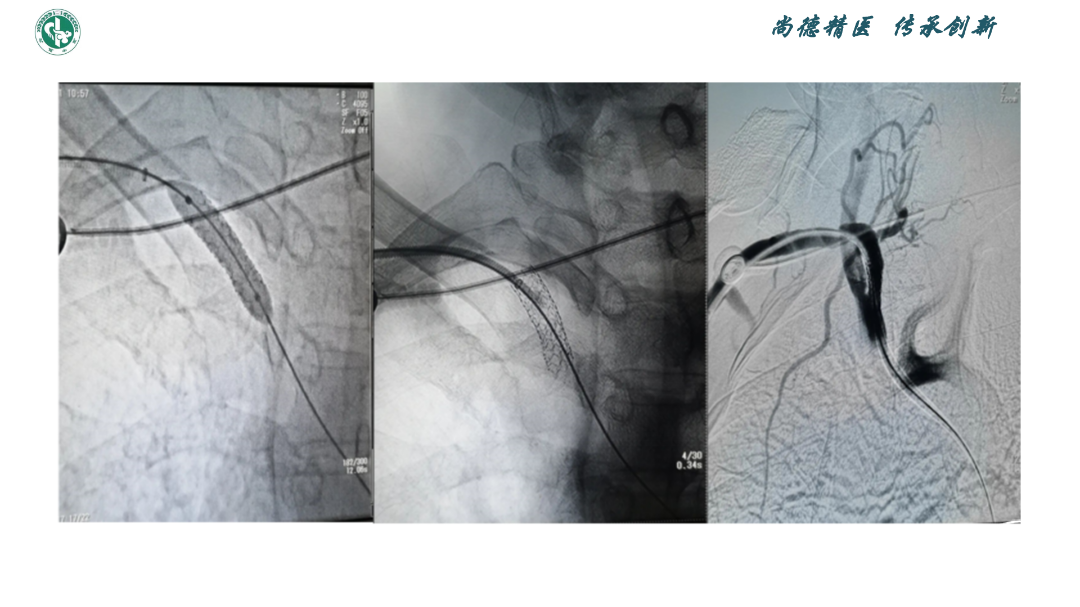

弓上血管狭窄的介入技术

赵宝元

武威市中医医院